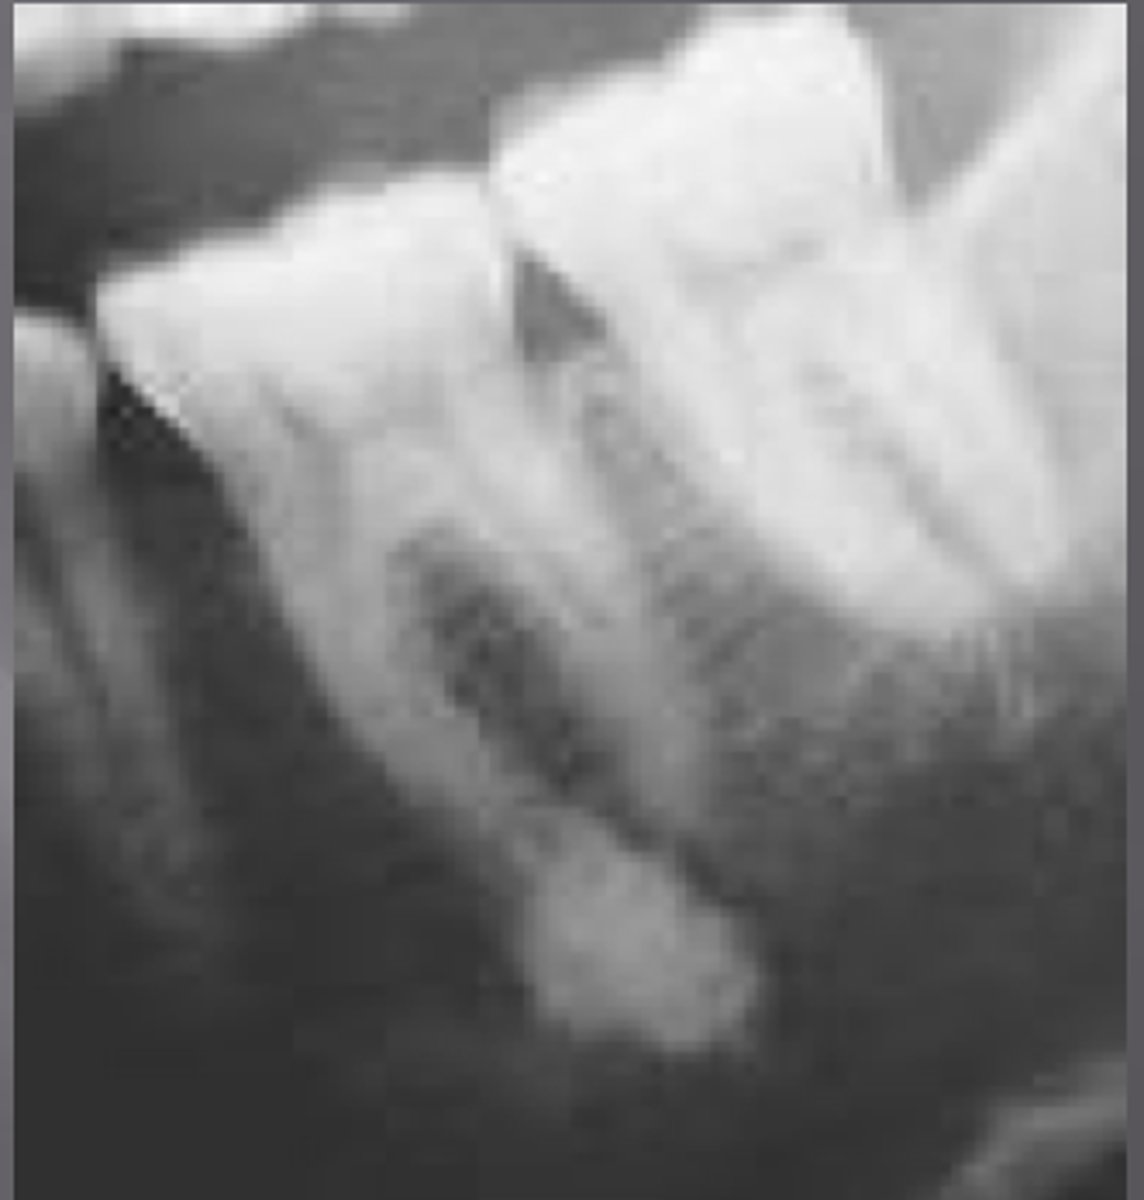

what is this?

what is this radiolucent area in the image?